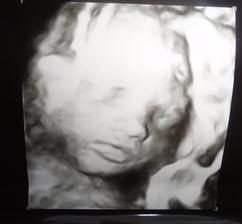

O anjelikovi a srdiečku